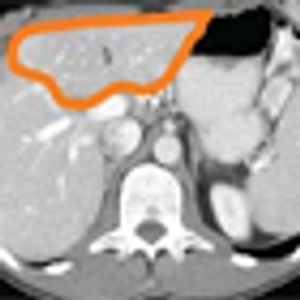

In a good percentage of patients who have oligometastatic disease confined to a single organ-usually the liver-complete metastasectomy can result in cure. However, once the decision to pursue surgery is made, there remain a number of issues that must be addressed in order to ensure the best possible outcome.